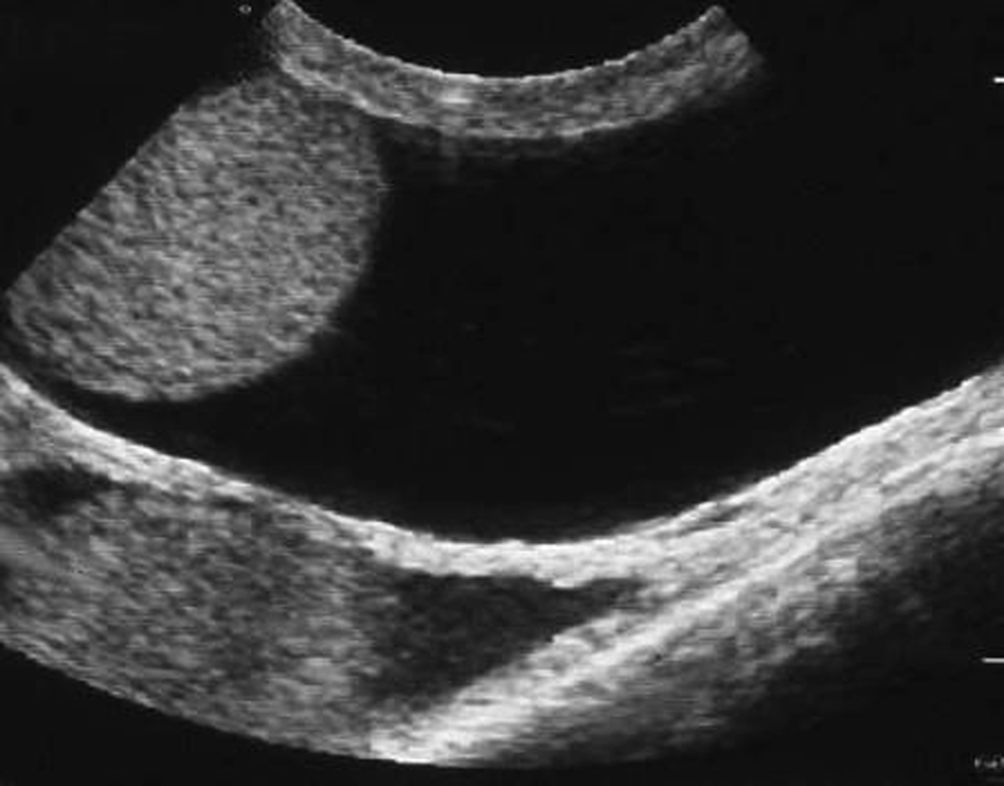

L’échographie montre :

- un épanchement trans-sonique de la vaginale entourant le testicule :

- en cas d’hydrocèle volumineuse sous tension, le testicule et l’épididyme sont refoulés dans la partie postéro-inférieure de la bourse et comprimés contre la vaginale (figure 28.3) ;

- en cas d’hydrocèle chronique, l’épanchement est échogène (cristaux de cholestérol en suspension) avec ou sans cloisons ;

- parfois, la présence de concrétions cholestéroliques, intravaginales mobiles ou d’épaississements nodulaires de la vaginale (figure 28.4).

Fig. 28.4. Hydrocèle vaginale ancienne : épanchement échogène et nodule de pachyvaginalite.

Source : CERF, CNEBMN, 2022.